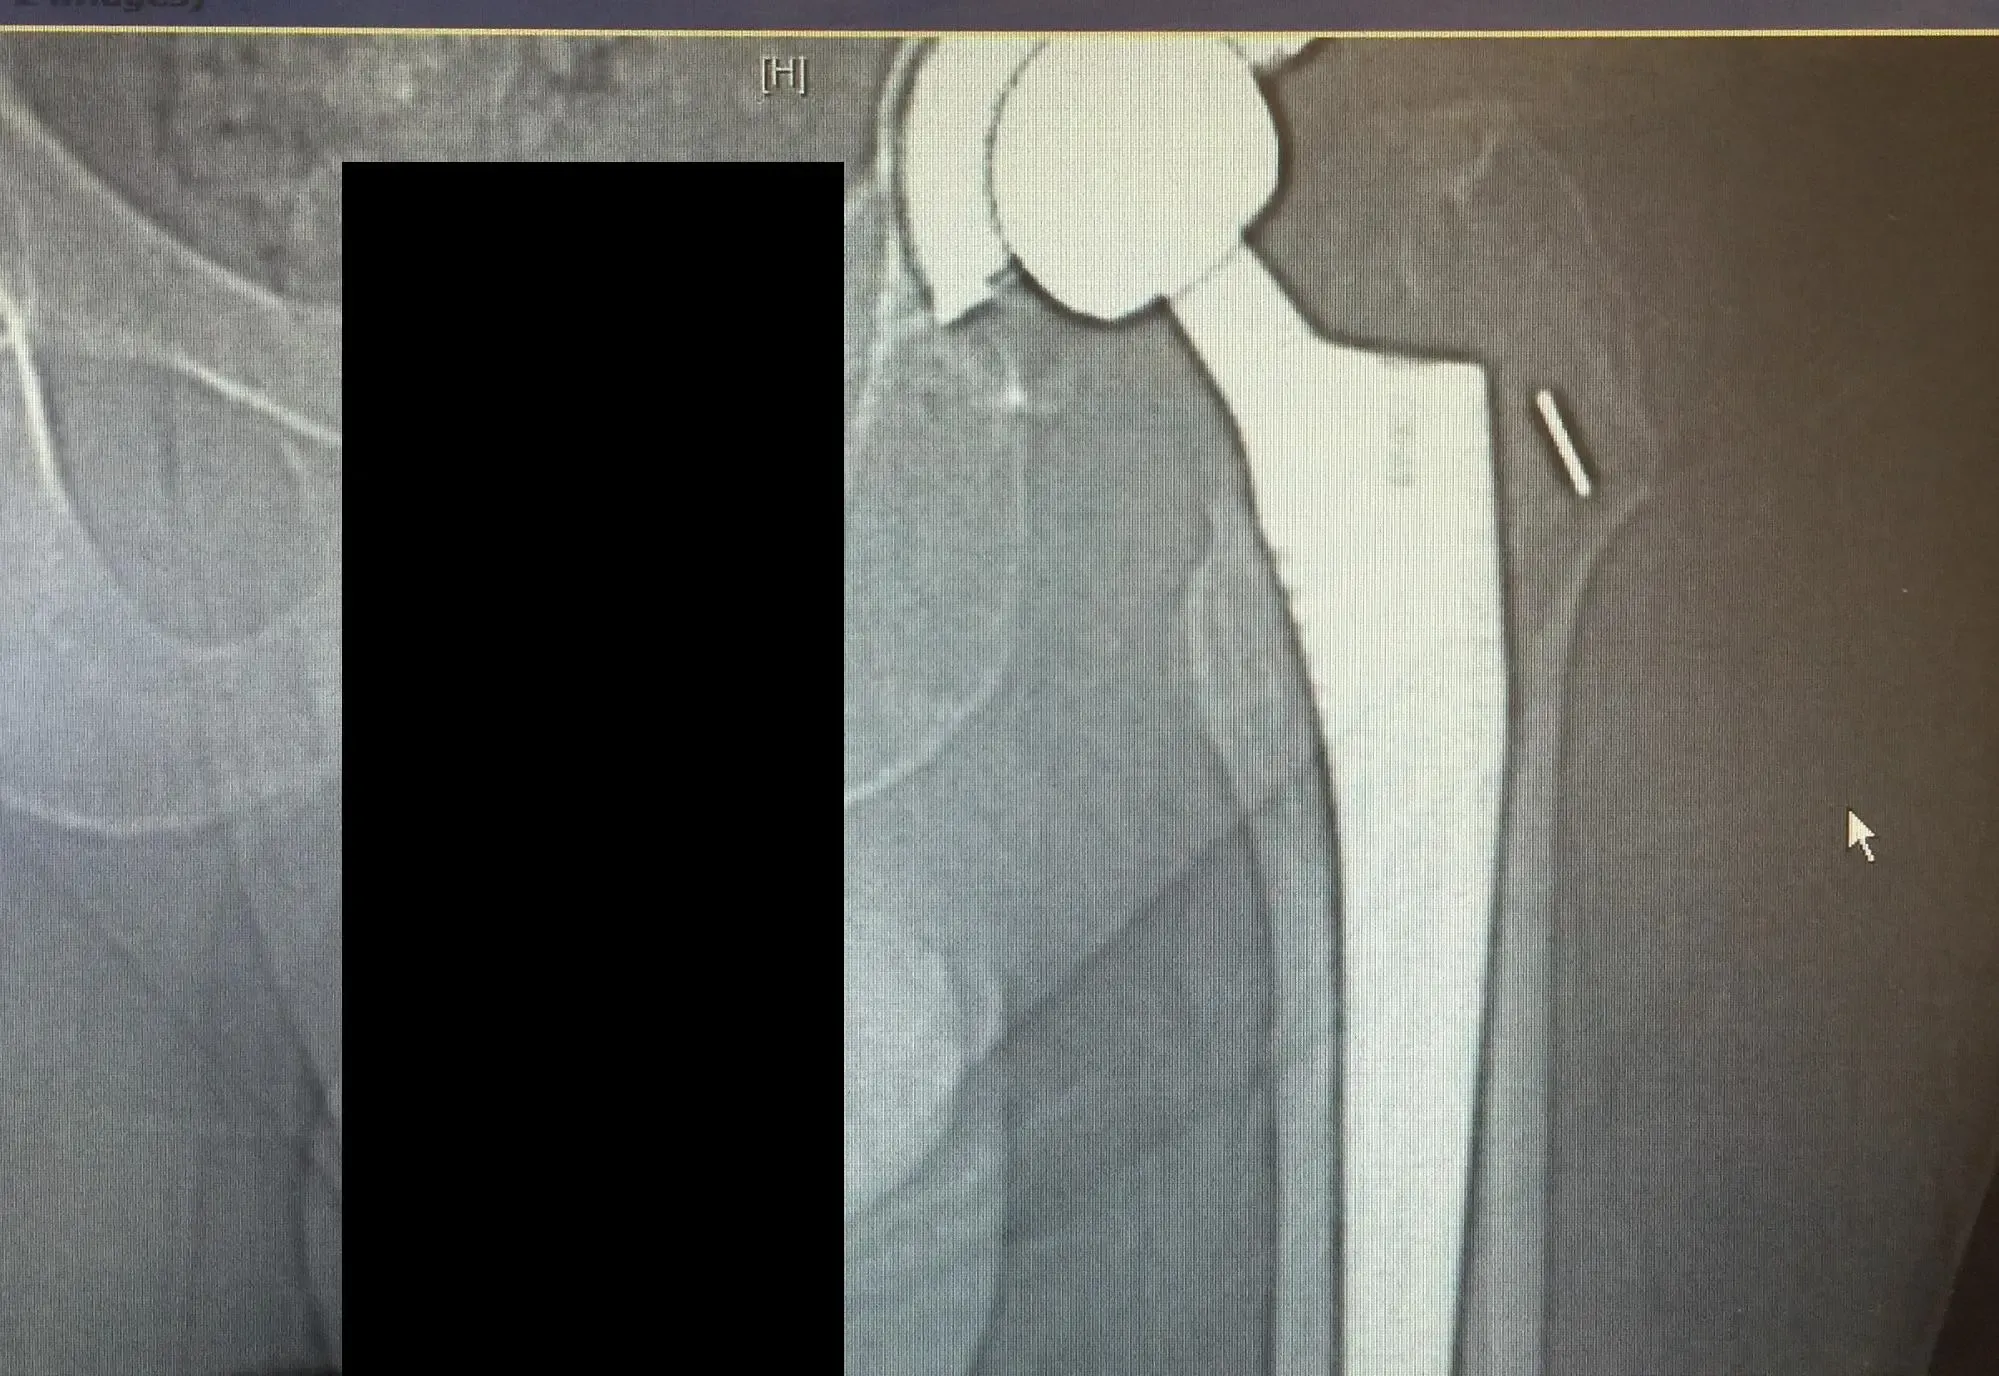

La tomografía computarizada y la radiografía de la cadera izquierda revelaron una fractura periprotésica no desplazada del fémur proximal anteromedialmente con subsidencia del tallo.